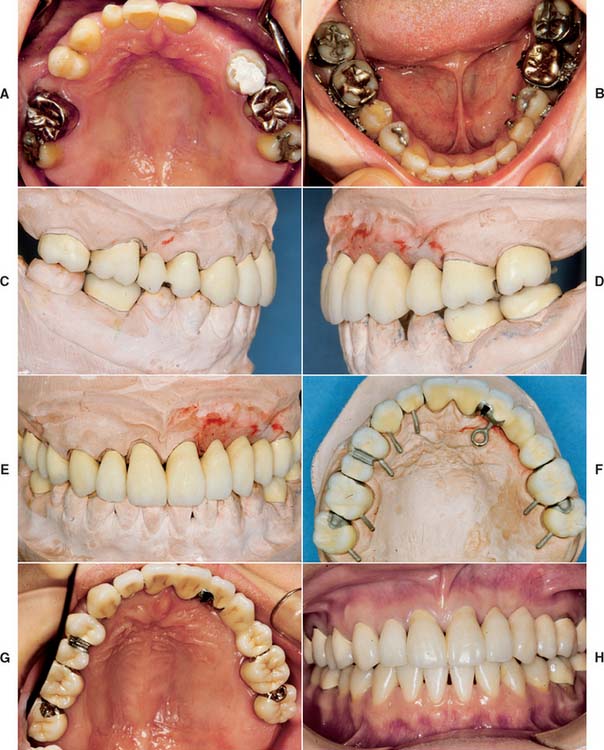

Several treatment results are presented, including follow-up documentation as appropriate, in some cases over many years. The treatments demonstrate successful treatment approaches that are consistent with the principles discussed throughout this text.

Fig. 32-38 Full-mouth rehabilitation with fixed, implant-supported, and removable partial prosthodontics (Treatment VI). Before treatment: Note the reverse smile line and discrepancy in the maxillary central incisor gingival tissue levels. The maxillary first molars had furcation involvement and poor prognosis as a result of periodontal bone loss. A and B, Occlusal views. C, Frontal view. D and E, Right and left views in maximum intercuspation. F, Diagnostic waxing. G, Dental implants were placed to restore the mandibular arch and provide retention and support for a maxillary partial removable dental prosthesis (RDP). H, The gingival tissue levels were corrected with periodontal surgery. I and J, Anterior teeth prepared for fixed restorations. After treatment: K and L, Occlusal views of maxillary arch with and without partial RDP. M, Occlusal view of restored mandibular arch. N and O, Right and left mirror views in maximum intercuspation. P, Frontal view.

Fig. 32-39 Extensive fixed prosthodontics (Treatment VII). Teeth with advanced periodontal disease restored with fixed prosthodontics. A, Initial presentation. The patient required extraction of the right maxillary incisor and surgical correction of the periodontal defects. B, Maxillary teeth prepared for metal-ceramic restorations. C, Reversible hydrocolloid impression. D, Interim restorations. E, Definitive casts. F, Anatomic contour wax patterns. G, Patterns cut back for porcelain application. H, Sprued patterns. I, Metal framework evaluation. J, Opaque porcelain applied. K, Bisque porcelain. L, Centric contacts are on metal. M, Finished restorations before cementation. The extensive prosthesis is segmented with intracoronal rests. N and O, Cemented prostheses.

Fig. 32-40 Extensive fixed and removable prostheses (Treatment VIII). A and B, The patient presented with missing maxillary anterior teeth and mandibular posterior teeth. There was a significant slide from centric relation to maximum intercuspation. The patient was treated with a combination of fixed and removable prostheses. C, Maxillary teeth prepared and foundation restorations placed. D and E, Maxillary teeth waxed to anatomic contour. F and G, Completed fixed restorations. H, Definitive cast for mandibular partial removable dental prosthesis (RDP) framework before duplication. A rotational path of placement was used to engage mesial undercuts in second molars. I, Completed mandibular RDP. Amalgam stops were placed in the first molars to prevent premature wear of the denture teeth. J, Completed treatment. K to O, Appearance 13 years after treatment.

Fig. 32-41 Anticipation of future needs (Treatment IX). A and B, Pretreatment photographs. C to E, Buccal/labial view of bisque bake. F and G, Occlusal view before and at clinical evaluation. Note the location of the occlusal rests to anticipate various future partial removable dental prosthesis designs. An intracoronal rest (dovetail) was incorporated in the left lateral incisor. It is filled with composite resin, which is easily removed if the need arises. H, Completed treatment.

Fig. 32-42 This patient presented with multiple failing restorations and severely compromised function (Treatment X). A to E, Preoperative photographs. F to J, Posttreatment photographs. Where possible, I-bars were used to minimize clasp visibility. Also note the extensive use of metal occlusal surfaces. When prostheses are designed for dentitions with compromised crown/root ratios, precise adjustment of the occlusion and anterior guidance components is critical. K to Q, Seventeen-year follow-up photographs. Note that the maxillary canine was lost and the existing retainer was modified into a pontic through the addition of composite resin. Additional endodontic treatment was needed as time passed. R, Preoperative radiographs. S, Postoperative radiographs. T, Eight-year postoperative radiographs. U, Seventeen-year postoperative radiographs. A fixed dental prosthesis (FDP) was fabricated, replacing the missing tooth #3 with teeth #5, #4, and #2 as abutments. The teeth were prepared with minimal taper, and the castings exhibited good retention. After 10 years, the FDP failed when tooth #2 became dislodged, possibly as a result of the additional loading by the removable dental prosthesis (RDP). Tooth #2 and the pontic were removed, endodontic treatment was performed, a new crown was fabricated, and the #3 pontic was incorporated in a new RDP. Tooth #6 was lost as a result of internal resorption and caries. Initially, the tooth was discolored, but the lesion was inactive, and the attempt to save it failed after 8 years. Its guarded prognosis was discussed as a significant risk factor before treatment initiation. This suggests that teeth with a guarded prognosis can be maintained if attention is paid to the principles of casting adaptation and occlusion.

Fig. 32-43 Long-term follow-up after comprehensive treatment with fixed prostheses of the patient in Fig. 32-41 (Treatment XI). A to E, Preoperative photographs. F to J, Postoperative photographs. K, Preoperative radiographs. L, Fourteen-year postoperative radiographs. If the fixed prostheses have been designed carefully and the patient is cooperative and maintains excellent plaque control, fixed dental prostheses can withstand the test of time. Today, these prostheses continue to provide excellent esthetics and function after more than 16 years of service. Note that no intervention was done for the impacted canine. Initially, this patient presented with only posterior guidance on the left and right first molars. A gingival graft was performed on the left side before the fixed prosthodontic treatment. Fourteen years later, all teeth are stable without any clinically significant mobility, and the anterior guidance components exhibit no visible faceting. No significant change has occurred in bone levels, whereas apparent radiographic bone densities appear slightly increased. Meticulous attention to precise adjustment of the occlusion, especially the anterior guidance component, contributed to the long-term success of this treatment. On the 14-year postoperative radiographs, no signs of occlusal trauma are seen. Also, note that three endodontically treated molars have very large access cavities. Such teeth have a guarded prognosis and are prone to fracture, but no fractures have occurred. Again, this suggests the importance of precise and optimal load distribution at the time of initial treatment and during periodic follow-up appointments. This patient was recalled every 6 months.

Fig. 32-44 Treatment of a severely periodontally compromised dentition (Treatment XII). A to C, Preoperative photographs. D to F, Fourteen-year postoperative photographs. In the initial discussion of an extensive treatment plan with a patient with a severely compromised dentition, the many risks and possibilities of failure must be fully understood by all parties. This extremely complex rehabilitation continues to serve well today. A meticulous design and frequent recall appointments, combined with outstanding home care, enables this patient to enjoy improved function 14 years later. Throughout the follow-up, the patient was seen at 1-month and periodic 3-month recall appointments, depending on pocket charting and patient motivation. Today, tooth #4 has no attached gingiva and little bone support, but no pocket formation. Initially, it was expected that this tooth would be the first to be lost. In conjunction with loss of tooth #1, this would have necessitated a partial removable dental prosthesis or implant-supported fixed dental prosthesis. Occlusal rests, undercuts, and guide planes had been incorporated in the initial prosthesis to anticipate such failure. After more than 14 years, the prostheses continue to serve satisfactorily. The anterior guidance component is starting to show some wear. Throughout the recall, wherever posterior tooth contact was observed in excursive movements, they were eliminated as part of ongoing occlusal adjustment. Meticulous management of load distribution has contributed to the long-term success of this very complex rehabilitation. G, Preoperative radiographs. H, Fourteen-year postoperative radiographs. This patient was referred initially for complete maxillary and mandibular denture fabrication. Before prosthodontic treatment, the periodontal condition was treated. Treatment included a modified Widman flap, performed throughout both arches. A root resection was done for tooth #14, and tooth #30 was hemisected, which resulted in two premolar-like restorations. Use of the severely tilted tooth #17 as a single abutment to support a very long span posed a substantial risk to the long-term success of this treatment, and the tooth’s future loss was anticipated in the design of the prostheses. Another risk was posed by the root structure of tooth #1, with a small, fused root. This tooth was lost after 14 years as a result of a periodontal defect that progressed along a vertical groove in the fused root.

Fig. 32-45 Long-term evaluation (Treatment XIII). A to E, Preoperative photographs. F to J, Eighteen-year posttreatment photographs. Three simple fixed dental prostheses combining conventional and metal-ceramic prostheses with postsoldered connectors continue to serve 18 years after initial placement. Complications over the years included the reshaping of some restorations to correct occlusal discrepancies and the endodontic treatment of tooth #19 through the prosthesis (the access cavity was restored with amalgam). This patient presented with congenitally missing teeth #4 and #12. The maxillary canine was left in the premolar position for use as an abutment with posterior disocclusion resulting from guidance on the canine-shaped pontic. This is not ideal from the perspective of force distribution; however, the canine root successfully withstood the loading over time. Risk factors initially discussed with the patient included uncertainty regarding the effect of the crown/root ratios on the long-term prognosis. At the time of prosthetic treatment, more than 25 years ago, osseous integration was not the reliable treatment modality that it is today. The young woman declined a removable prosthesis as an alternative to fixed dental prostheses. A pinledge retainer was used on the small lateral incisor. Over time, not only was this esthetically effective, but it contributed to long-term maintenance of its periodontal health. Similarly, a pinledge was used on the left mandibular canine, a far more conservative option than a metal-ceramic restoration. If instead metal-ceramic retainers had been used, by now this likely would have resulted in additional treatment needs and possibly the loss of the lateral incisor. Teeth #18, #19, and #3 were treated endodontically; cast posts and cores were used. Also, note that tooth #8 has served well over time. The conservative access cavity was restored, and the favorable position in the arch results in favorable loading. Recall appointments for this patient were scheduled at 6-month intervals throughout the evaluation period. K, Preoperative radiographs. L, Eighteen-year postoperative radiographs.